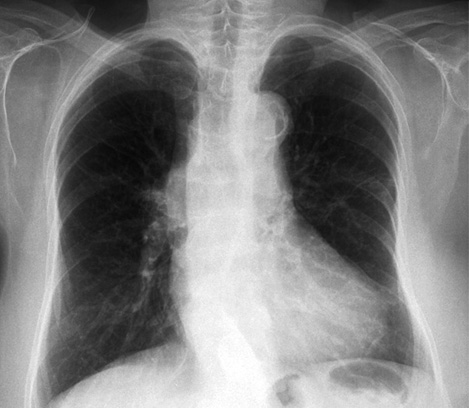

- Radiografía de Tórax: puede ser normal o demostrar cardiomegalia leve y calcificación de la aorta.